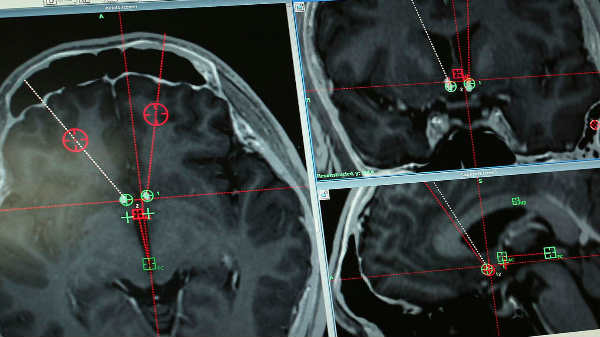

பழமொழிகளில் கூறுவது போல எப்போதும் அறிவியல் புனைகதைகளை காட்டிலும் உண்மை அந்நியம் தான். அதுபோல புனைகதை. சீனாவில் உள்ள விஞ்ஞானிகள் போதைபொருளுக்கு அடிமையானவர்களுக்காக, மருத்துவ பரிசோதனை மூலம் உலகின் முதல் ஆழ்ந்த மூளை தூண்டுதலை (DBS-Deep brain stimulation ) மேற்கொண்டு சாதனை படைத்துள்ளனர்.இதிலுள்ள துளையிடும் நடைமுறையில் நோயாளியின் மண்டை ஓட்டில் இரண்டு துளைகளை இட்டு, அவர்களது மூளையில் இரு எலெக்ட்ரோட்கள் வைக்கப்படுகிறது. இதை ஒரு கையடக்க சாதனத்தால் மின்னணு முறையில் தூண்டமுடியும்.

அறிவியல் புனைகதை திரைப்படங்களில் வருவது போல, மண்டல ஓட்டில் துளைகள் இட்டு இரு சிறிய எலக்ட்ரோடுகள் அடிமையாக்கும் பின் மூளை பகுதியில் படும்படி பொருத்தப்பட்டுள்ளது. சிலமணி நேரம் கழித்து நடைபெற்ற மற்றொரு அறுவைசிகிச்சையில் அவரது மார்பு பகுதியில் பேட்டரி ஒன்று பொருத்தப்பட்டது.

பேட்டரியின் மூலம் எலக்ட்ரோடுகள் செயல்படத்துவங்கியதும், டேப்லெட் கருவி மூலம் அவரது மூளையை தொலைதூரத்தில் இருந்து கட்டுப்படுத்தி சாதனை படைத்துள்ளனர்.